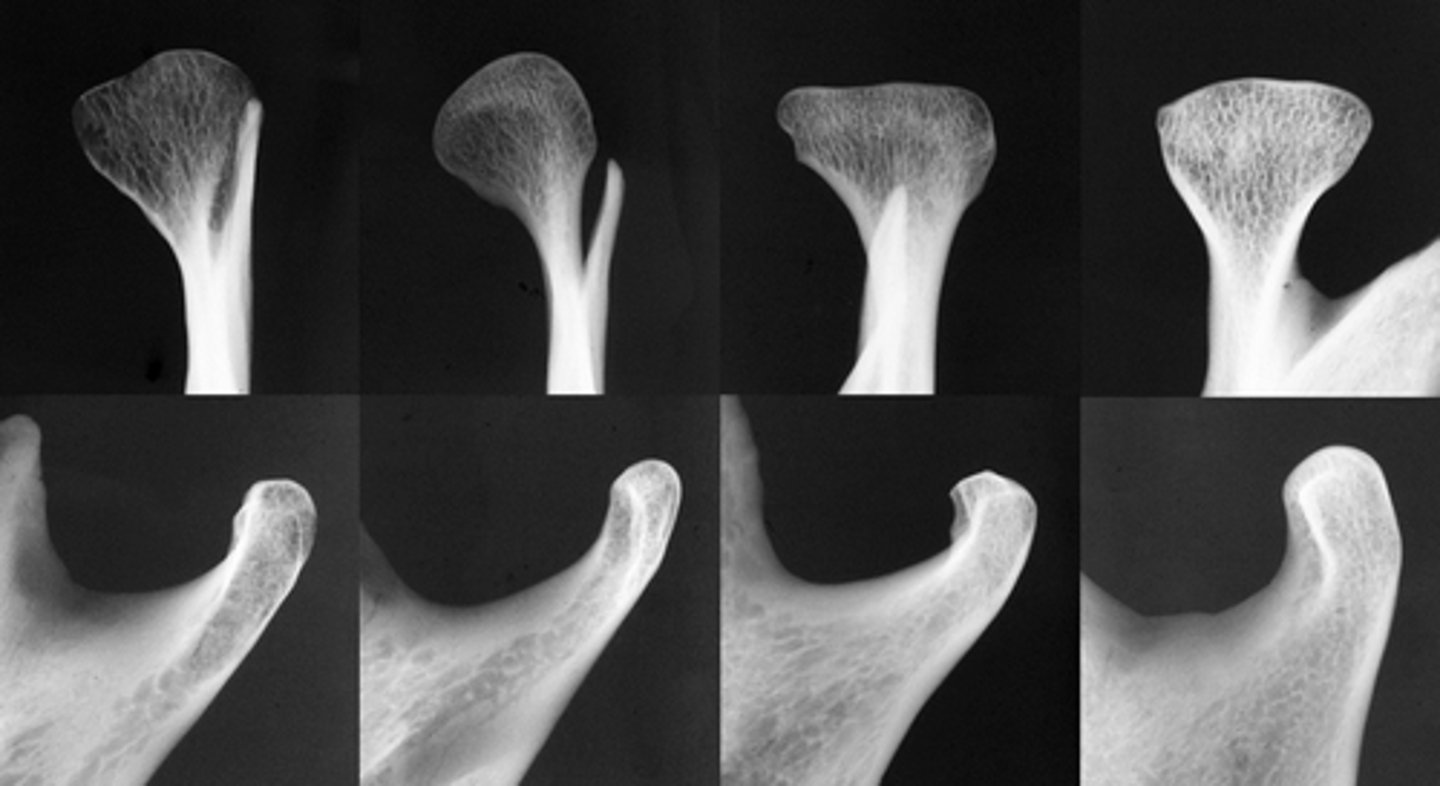

Patient has DJD.

The top images show the subchondral/ Ely cyst, a pseudocyst of connective tissue, granular tissue and osteoid, the bottom images show the same patients left side with broad erosion, a lack of cortication, loss of joint space.

What is the diagnosis of the patient based off these radiographs and what are the features? (Top images = patients right condyle) (bottom images= same patients left condyle)

Osteophytes- joint mice associated with DJD

What are the arrows showing?

Patient has DJD, there is significant erosion and loss of joint space.

A and B show prominent osteophyte formation at the anterior aspect

C shows multiple subchondral erosions

What is the diagnosis of the patient based off these radiographs and what are the features?